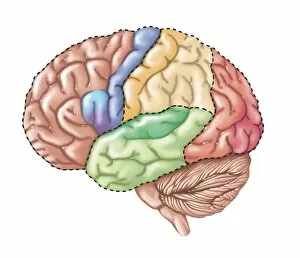

The central nervous system, the intricate network that governs our every thought and movement, is a marvel of complexity. From the delicate cerebellum tissue to the detailed light micrograph capturing its essence, we are reminded of its importance in maintaining balance and coordination. Anatomy comes alive as we explore the human brain from an inferior view. The intricacy of brain fibers is revealed through DTI MRI scans like C017/7099 and C017/7035, showcasing their vital role in transmitting information throughout this extraordinary organ. Artistic renderings bring us closer to understanding the medulla oblongata's significance within the brain. Its portrayal in various artworks allows us to appreciate how it controls essential functions such as breathing and heart rate. As we delve deeper into studying the central nervous system, models of the human brain provide invaluable insights into its structure and organization. Lateral views reveal countless regions responsible for cognition, emotion regulation, sensory perception, and motor control. Microscope slides offer glimpses into nerve cells' intricate architecture—a testament to their ability to transmit electrical signals at lightning speed. Meanwhile, glial stem cell cultures captured under a light microscope remind us of their crucial role in supporting neuronal function. Finally, artistic representations unveil the limbic system's enigmatic nature—an interconnected web responsible for emotions and memory formation. These captivating artworks allow us to visualize this complex network within our brains. Exploring these hints provides a glimpse into the awe-inspiring world of our central nervous system—the very foundation upon which our thoughts, actions, memories reside—reminding us just how remarkable our brains truly are.